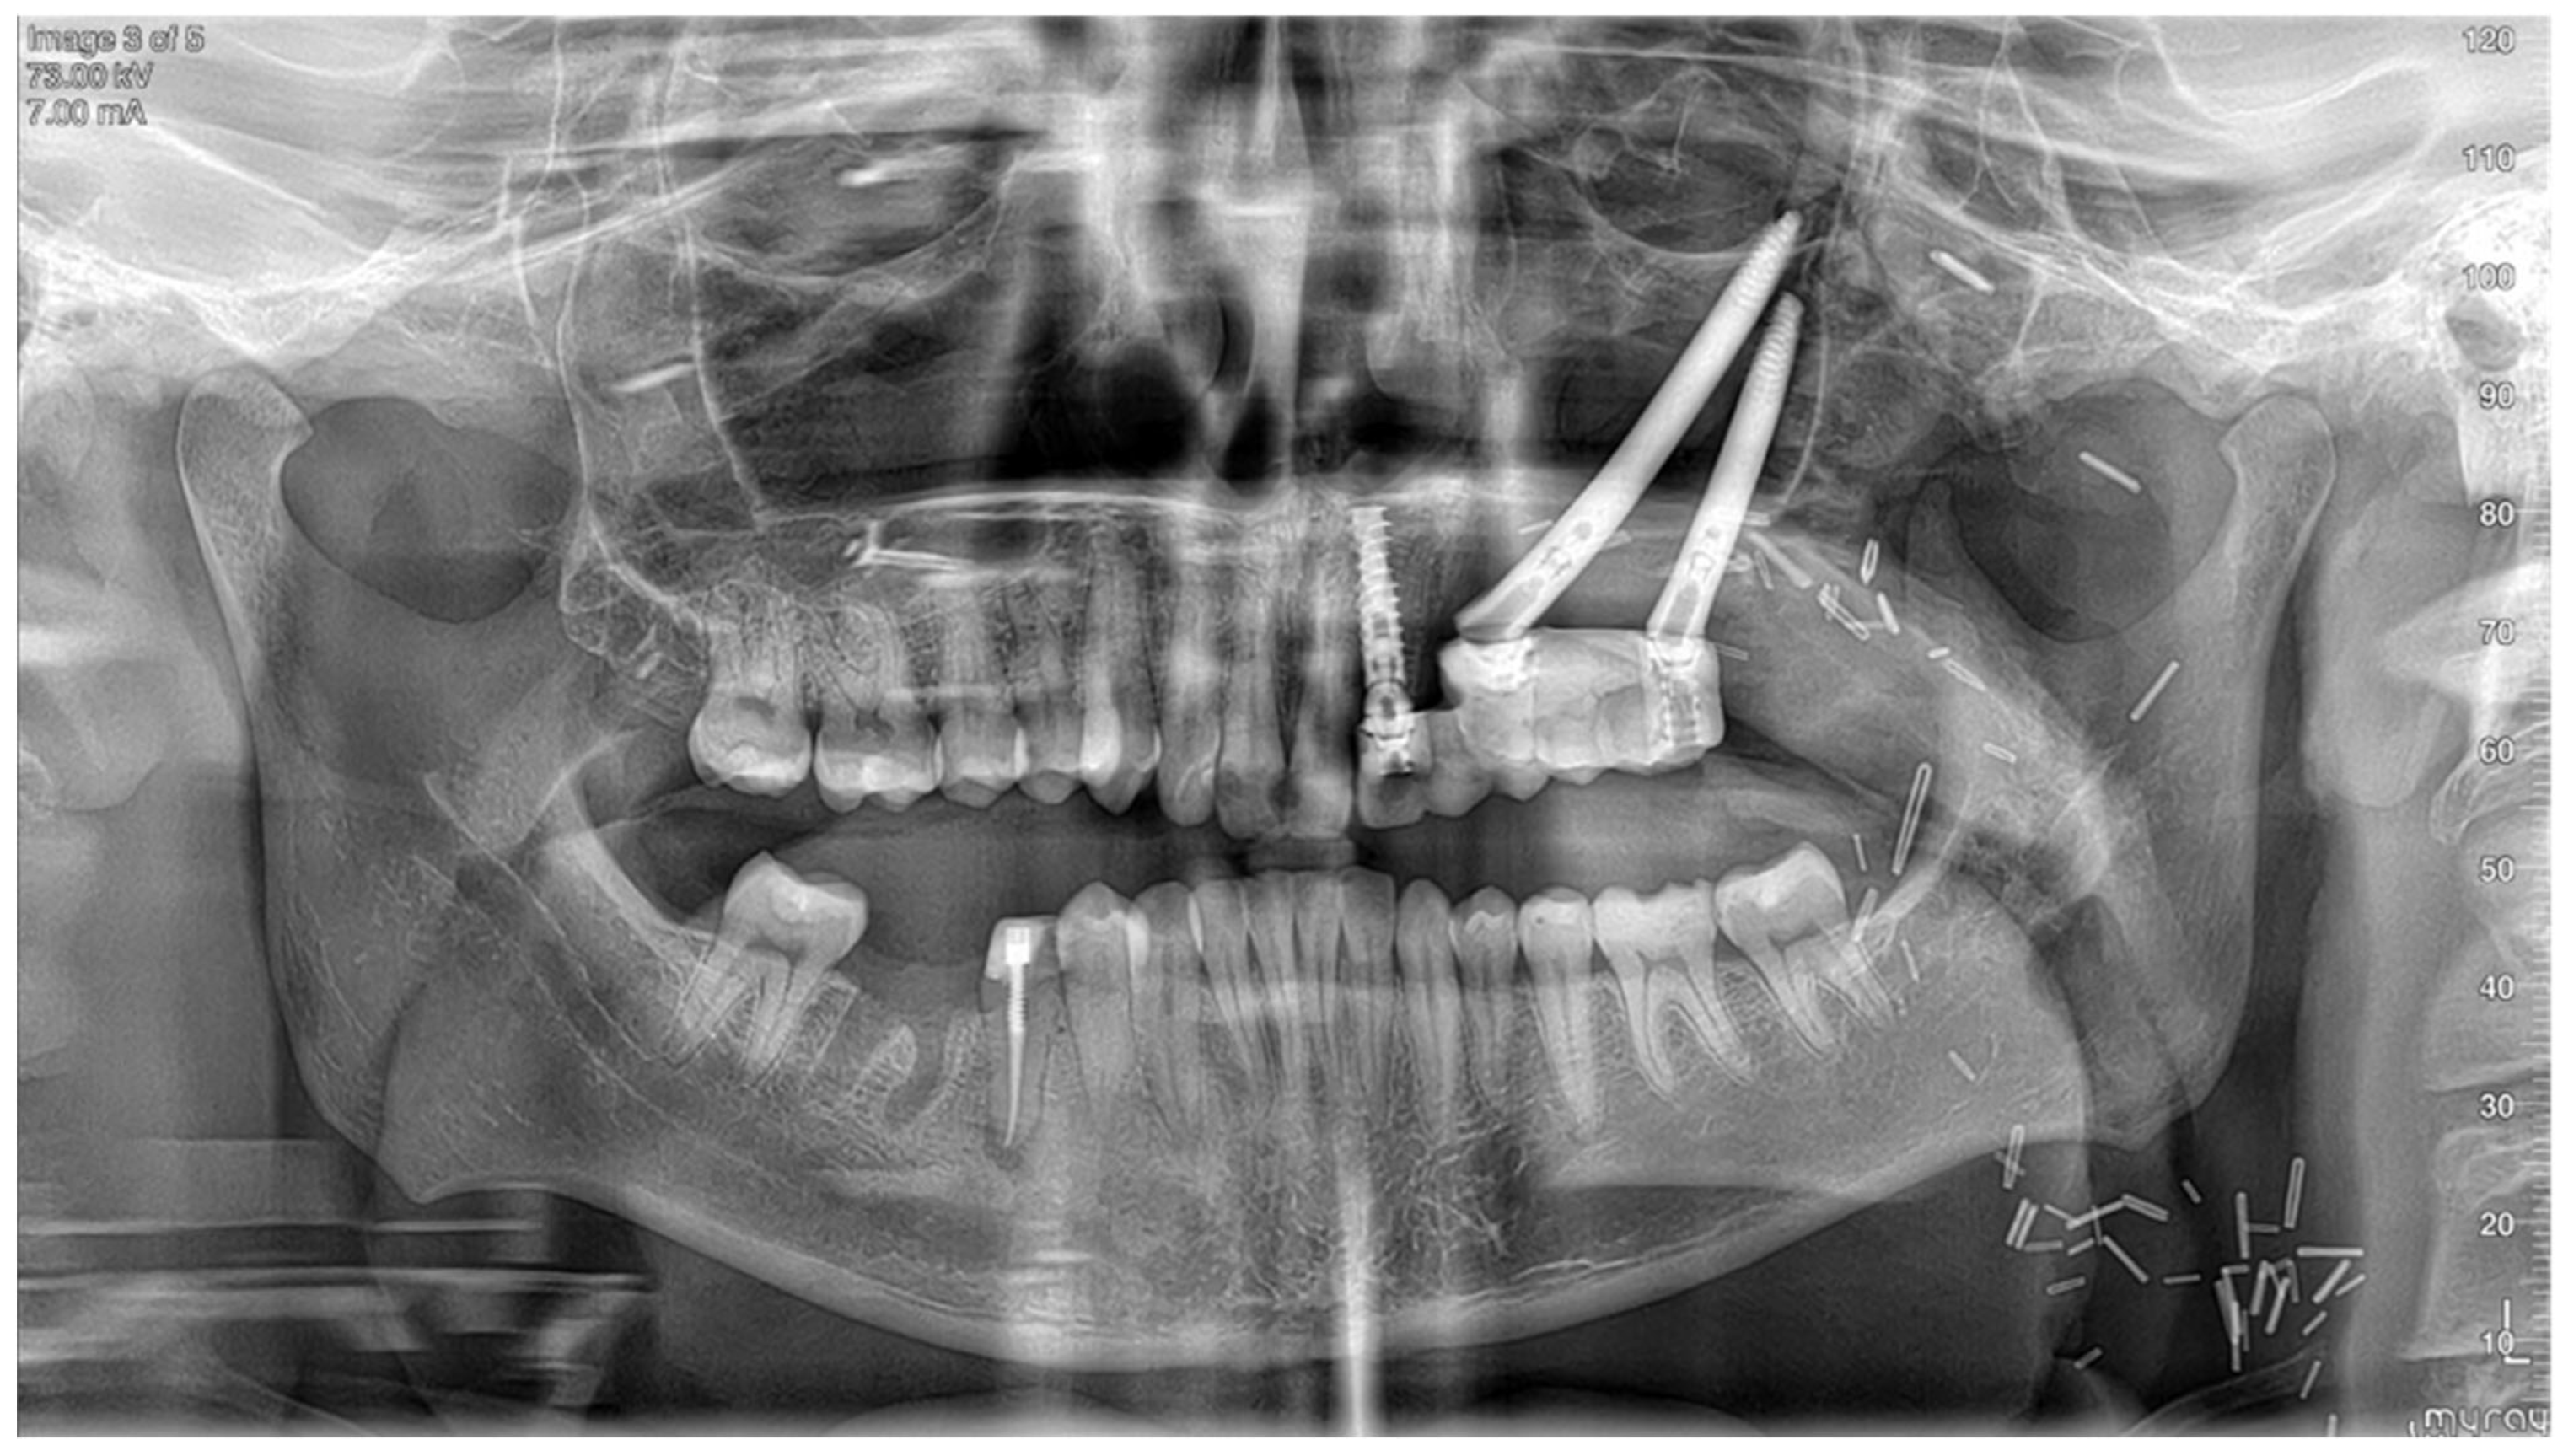

- Implant planning: Using a dental scan of both jaws, plan the positions of zygomatic implants and abutment emergence to fit the dental arch and occlusion. As a guideline, we aim for 15 mm vertical distance between the implant platform and opposing teeth.

- Surgical guide preparation: Plan a surgical guide for both zygomatic and standard implants (Figure 9). Ensure that the guide fits accurately to the post-resection maxillary and zygomatic defect boundaries. We recommend printing a 3D model to help the surgeon visualize the expected surgical defect (Figure 10). For cases with high uncertainty, surgical cutting guides can be printed (though they were not used in this case).

- Immediate restoration: Following free flap anastomosis, the prosthodontic team can proceed with immediate dental restoration. This restoration can be planned using CAD-CAM, based on the planned zygomatic implants, abutment emergence, and the patient’s occlusion.